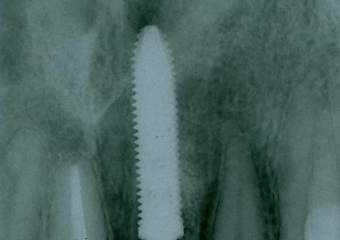

Raio X com implante e prótese provisória fixa